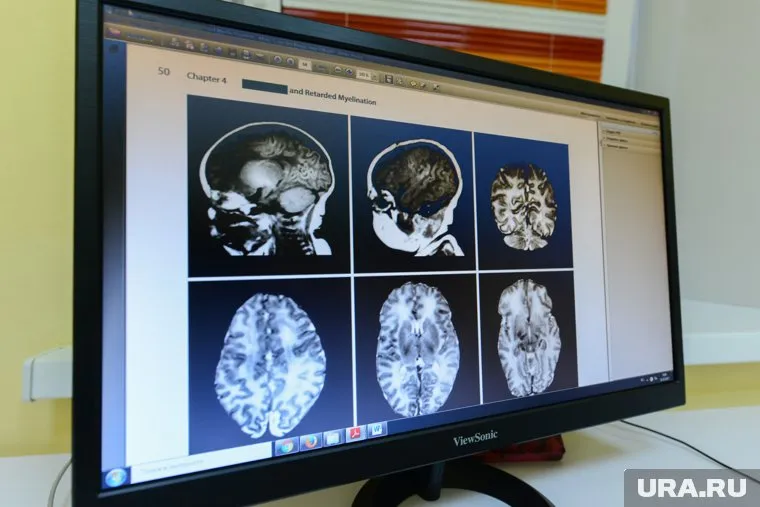

Фото: Фото: Вадим Ахметов © URA.RU

34-летний житель Британии скончался от неоперабельной глиобластомы вскоре после рождения третьего ребенка, изначально не обратив внимания на тревожные симптомы. Головные боли и спутанность сознания проявились у мужчины сразу после появления младшей дочери, но врачи посчитали их обычным стрессом.